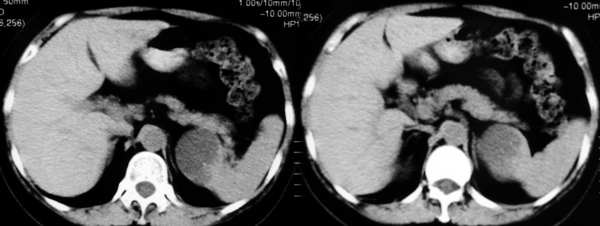

应该为脾脏来源的,囊性肿瘤,从前后ct片显示,有轻度强化改变(ct值),但好像有快速消退的感觉???

mr示脾内缘类圆形长t1长t2信号影,边界清楚

ct示脾内缘囊性低密度影,强化后其边缘实质部分与脾同步,且强化程度一样,

考虑脾囊肿

脾脏来源的,低密度,边界清,有分隔,有强化。

考虑:脾脏血管内皮瘤。

左侧肾上腺受压,病变不是来源于肾上腺,mri脂肪抑制病变为高信号,除外脂肪瘤,考虑来源于脾脏可能性大,强化后壁与脾脏强化基本相似,其内见分隔,囊腺瘤,血管瘤不除外。

cor上显示病灶与肾上腺无关,stir仍呈高信号,增强ct扫描各期均为低密度,且感觉张力较高,还是符合脾脏囊肿性病变的表现。

首先病灶的部位位于脾脏,这一点应该可以达成共识,因为它相邻的实质部分与脾脏同期.同时强化,并可见“鸟嘴”征象。第2:囊性病灶没有明显强化,在延期扫描的时候也是一样。也无病灶缩小的特征。所以我感觉应该考虑:脾脏囊性占位(脾脏囊肿可能性大)

同意大多数同仁意见,关键在于+c上明显显示脾动脉一分支走向囊肿边缘,同时与肾上腺无关.